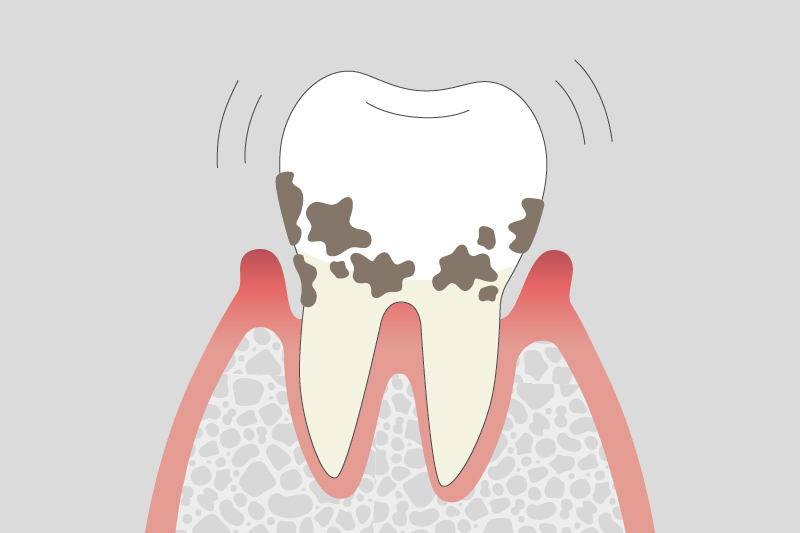

04.

重度歯周炎

歯槽骨の吸収が進み、歯の揺れが大きくなります。噛むと強い痛みが出る場合もあり、適切な治療を行わないと歯が抜ける原因となることがあります。